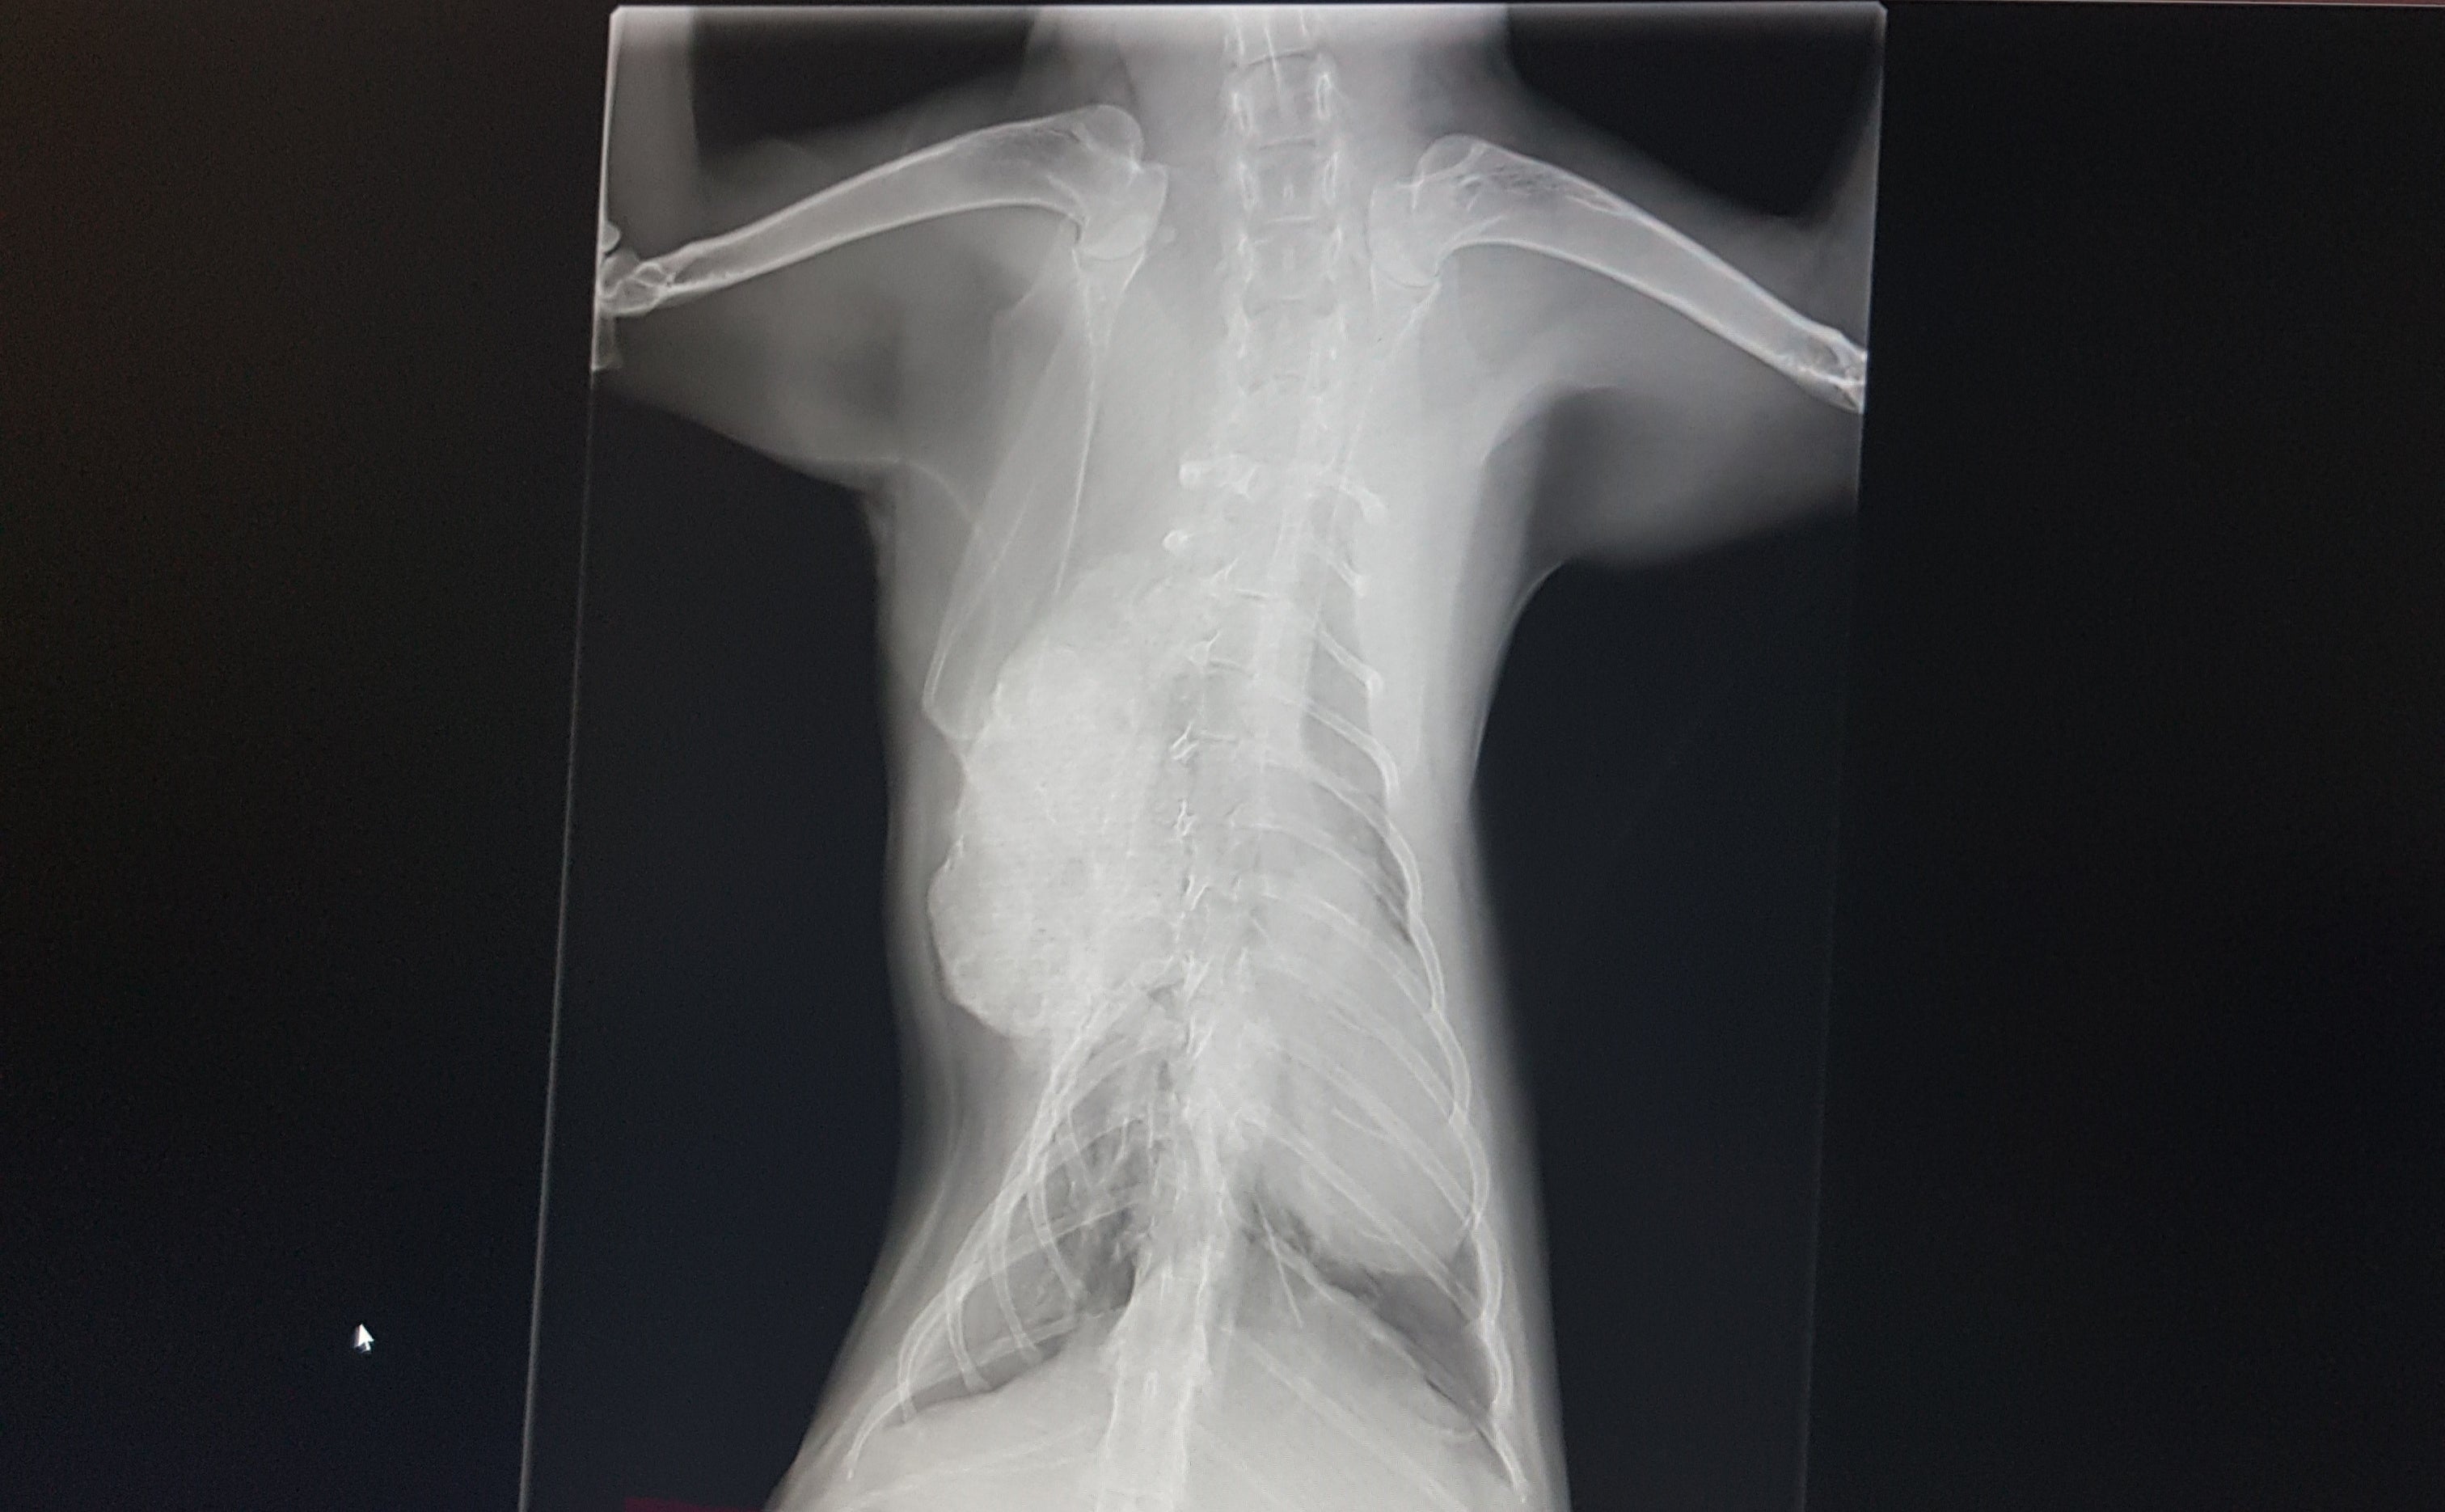

猫ちゃんの癌が再発しました。

顕微鏡単位で取りきれていなかった腫瘍が

同じ場所から大きくなり

手術で肋骨を切除していたため

前回よりも内側に腫瘍が入り込むような形で、気付くことが出来るようになるまで時間がかかりました。

検診は半年後で、半年になる前には気付くことが出来ましたが

腫瘍の成長スピードが早く

もう手術は出来ない状態でした。

猫ちゃんには珍しい癌で、症例も少なく